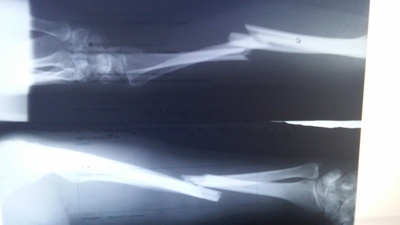

А как он, упав на отведенную руку, сломал обе? Оо

раскрыть ветку (4)

Автор поста оценил этот комментарий

Это вроде две проекции одной руки

Снимок сделан с двух сторон руки

нет одну. два снимка

раскрыть ветку (1)

Понял, не заметил сначала)

аппарат для того что бы кости ровно срослись, там было смещение и раздробление одной из костей. ну и чтобы руки одинаковой длинны потом были))